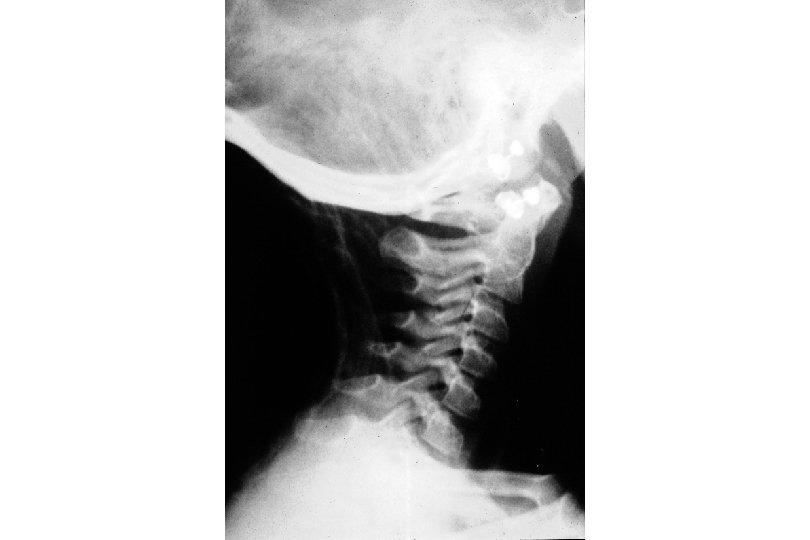

Pediatric Cervical Spine fulcrum is at C 2 -3 growth plate of dens weak neck muscles large head increases momentum SCIWORA because of ligamentous laxity most fractures occur at C 1 -2 difficulty with immobilization: large head/small chest allow for excessive flexion in supine position